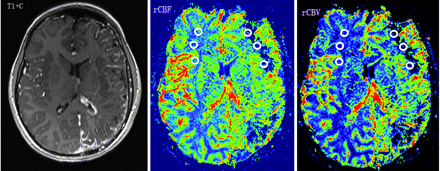

A 10-year-old girl with developmental delay (IQ = 55) and monthly seizures (patient 3 in On-line Tables 1 and 2). Contrast-enhanced T1WI (T1+C) shows left hemisphere volume loss and characteristic leptomeningeal enhancement in the same region, as well as a prominent left choroid plexus. PWI demonstrates decreased rCBF and rCBV (CBF-AIs = −0.67, CBV-AIs = −0.52) in the left frontal and occipital WM regions, underlying the leptomeningeal angiomatosis. Regions of interest placed on the affected left frontal WM and contralateral homotopic region are demonstrated.

In the SWS group, CBF-AIs varied between −0.82 and +0.39, whereas CBV-AIs varied between −0.67 and +0.69. All CBF-AIs values were considerably outside the normal range (the smallest AI was −0.12, consistent with a 12% asymmetry), and patients were divided into 2 subgroups according to their CBF-AIs values: an rLP group (negative CBF-AIs, indicating abnormally low perfusion on the angioma side; n = 9; Fig 1) and an rHP group (positive CBF-AIs, increased perfusion on the angioma side; n = 5; Fig 2). Detailed results are listed in On-line Table 2. It should be noted that 4 of the 5 children with high perfusion had a history of seizures, but all 4 were free of clinical seizures for at least 4 months before the MR imaging scan.